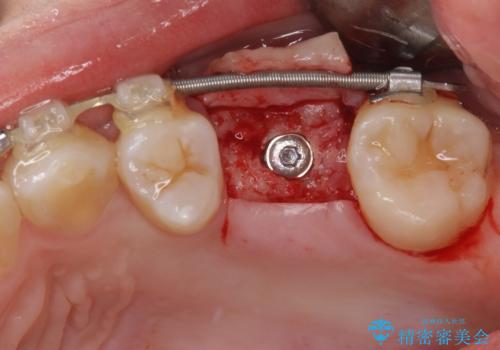

舌のトレーニングをしっかりと行っていただきながらワイヤー装置により矯正治療を行い、途中でインプラントを埋入し、矯正治療後に補綴治療を行うこととしました。

- 外科手術のため、術後に痛みや腫れ、違和感を伴います

- メンテナンスを怠ったり喫煙により、お口の中に大きな悪影響を及ぼすインプラント周囲炎等にかかる可能性があります